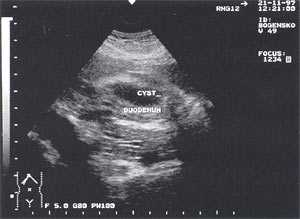

Оментобурсит (рис. 3) встречается в 28,4% случаев (из них 48% у мужчин и 52% у женщин). Некоторые авторы обозначают эту патологию как "псевдокиста поджелудочной железы". Отмечен объем таких образований от 5мл (малые объемы необходимо дифференцировать с сосудистыми аневризмами) до 3 л и более. Скорость формирования оментобурсита при остром панкреатите от 2 - 4 дн. от начала заболевания до 2 - 4 нед. При ультразвуковом исследовании оментобурсит представлен в виде анэхогенного образования с четкими контурами, неправильной или округлой формы, чаще с однородной структурой, с толщиной стенок 0,2 - 0,4 см. При эхографическом мониторинге утолщение стенки до 0,5 - 1,0 см с появлением неоднородности структуры следует расценивать как сонографический признак абсцедирования.

Рис. 3. Псевдокиста поджелудочной железы при остром панкреатите в виде анэхогенного образования с четкими контурами, однородной структурой, с наличием гиперэхогенных включений (детрит поджелудочной железы).